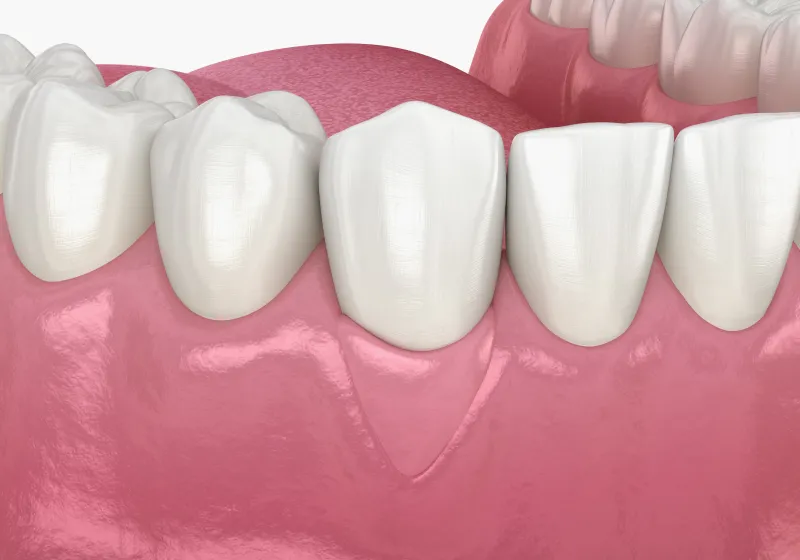

症例 Case

-

歯間の「黒い隙間」を修復|

40代 女性

歯間乳頭再建による審美性と機能性の回復

治療名 【重度歯周病】歯周組織再生療法による機能回復 治療期間 約1年(初期治療・経過観察期間含む) 執刀医 Dr. 大杉 治療費 250,000円(税込) 治療解説 一般的に抜歯適応と診断されやすい状態でしたが、歯の保存を優先して歯周組織再生療法を行いました。

事前にプラークコントロールと歯石除去を徹底し、炎症を安定させたうえで外科処置を実施。

結果として抜歯を回避し、長期的な機能維持を目指せる状態へ改善しました。リスク・副作用 術後に一時的な腫れや痛みが生じることがあります(鎮痛剤等の処方で管理を行います)。

また、喫煙等の生活習慣によっては治癒不全のリスクが高まる場合があります。 -